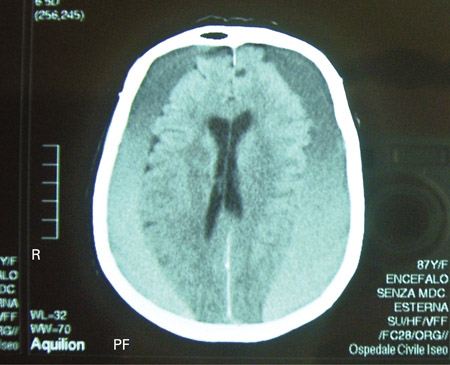

Hematoma subdural

TC cranioencefálica de um homem de 80 anos de idade com anormalidades da marcha e comprometimento cognitivo progressivo por cerca de 6 meses, mostrando um hematoma subdural crônico bilateral acima da convexidade cerebral

Adaptado de BMJ Case Rep. 2009;2009:bcr06.2008.0130